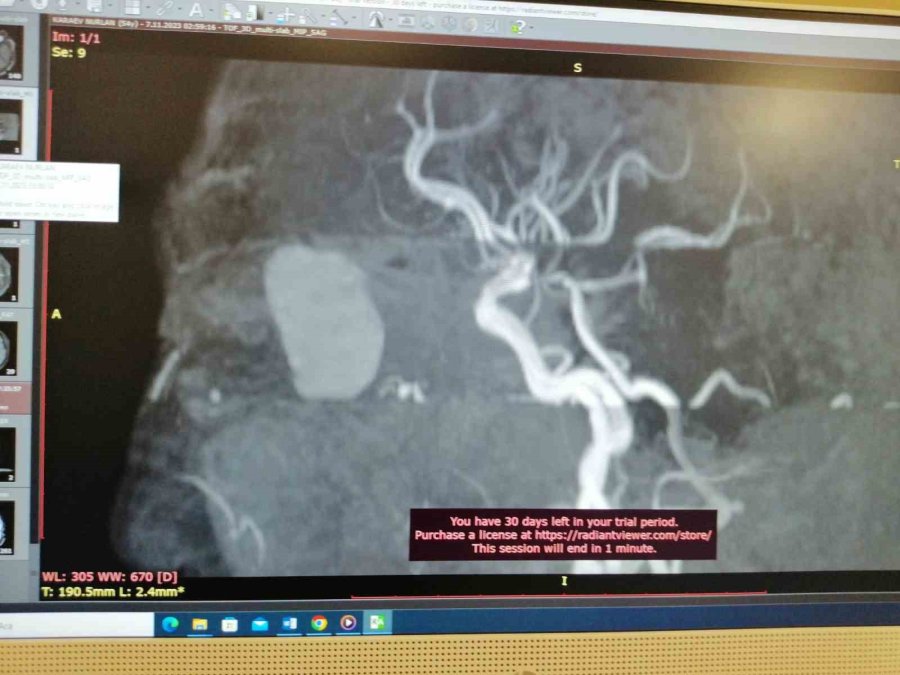

Yaptıkları tetkiklerde Karayev'in gözünde ciddi derecede görme kaybı olduğunu belirlediklerini kaydeden Uysal, "Tomografi ve MR'lar çekildi. Gözün arkasında orbita dediğimiz yerde kitle olduğu görüldü. Ona yönelik tedaviye başlandı. Bu tedavi olmasaydı, kitle görme sinirine bastığı için muhtemelen göz kör olacaktı. Aynı zamanda bu mukosel beyine doğru ilerleyecekti, daha büyük hasarlar verecekti" diye konuştu.

Hastaya mukosel tanısı konduktan sonra tedaviye başladıklarının altını çizen Uysal, "Sonra cerrahi olaraktan endoskopik sinüs cerrahisi var. Burundan girilerek göz arkasındaki kitleye ulaşıldı. Göz, orbita dediğimiz alandaki kitle çıkarıldı. Operasyonumuz 1,5 saat sürdü. Hastamızın şu an sağlık durumu gayet iyi. Artık sadece takip sürecimiz olacak" dedi.